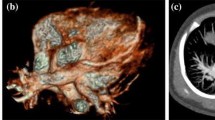

A 16-month-old boy with the diagnosis of pulmonary atresia with the fistula between the proximal RCA and MPA. Prospective ECG-triggering DSCT was performed at 80 kV and 80 mAs (effective dose, 0.43 mSv). (a) Multiplanar reformatted image and (b) volume-rendered image (anterior view) show the fistula (thick arrow) between the proximal RCA and MPA. (c) Thick-section oblique sagittal MIP image shows the ventricular septal defect (VSD) and overriding aorta. (d) Volume-rendered image (posterior view) shows two MAPCAs (slim arrows) arising from the DA. AA = ascending aorta, RCA = right coronary artery, MPA = main pulmonary artery, RPA = right pulmonary artery, RV = right ventricle, LV = left ventricle, MAPCA = main aortopulmonary collateral artery, DA = descending aorta

Completed transposition of the great arteries with a coronary artery anomaly in a 4-year-old girl. Prospective ECG-triggering DSCT was performed at 80 kV and 120 mAs (effective dose, 0.58 mSv). (a) Thick-section MIP image and (b) volume-rendered image (posterior view) show that both the right coronary artery (RCA) and left coronary artery (LCA) arose from the non-coronary sinus of Valsalva with a common ostium (arrow). AA = ascending aorta, MPA = main pulmonary, LA = left atrium